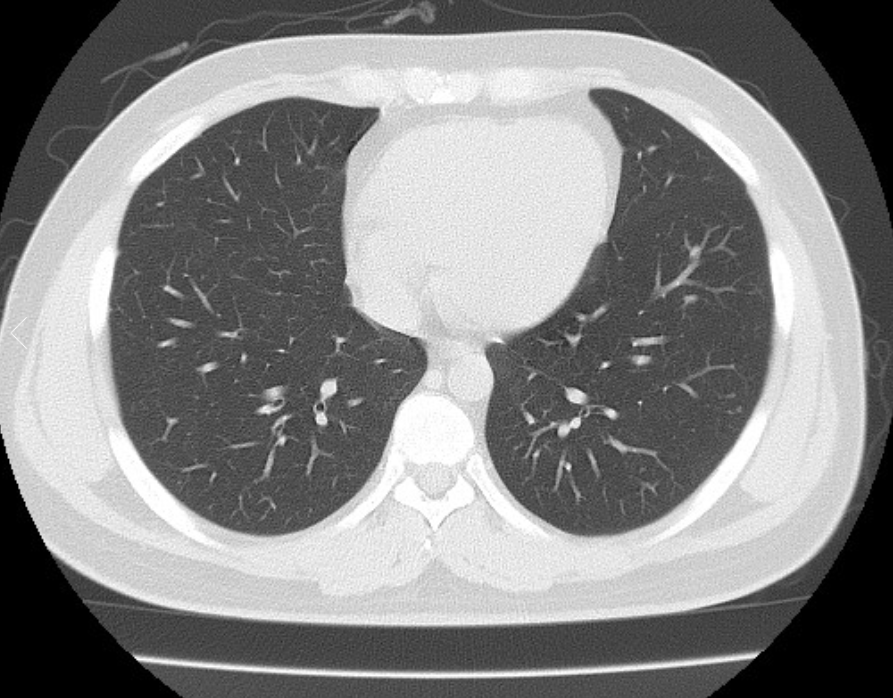

폐ct사진 받았는데 엄청 많더라구요.. 우중엽(40#)에 부분고형결절(6mm, 고형 2mm)결절이 있다고 소견을 받았는데 아래 ct사진 상 위험한 결절로 보이는지 판독좀 부탁드리겠습니다 ㅜㅜ. 다른 사진들 더 많지만 앞뒤 전후로 몇장씩만 가져왔어요..

• 2번 째 사진